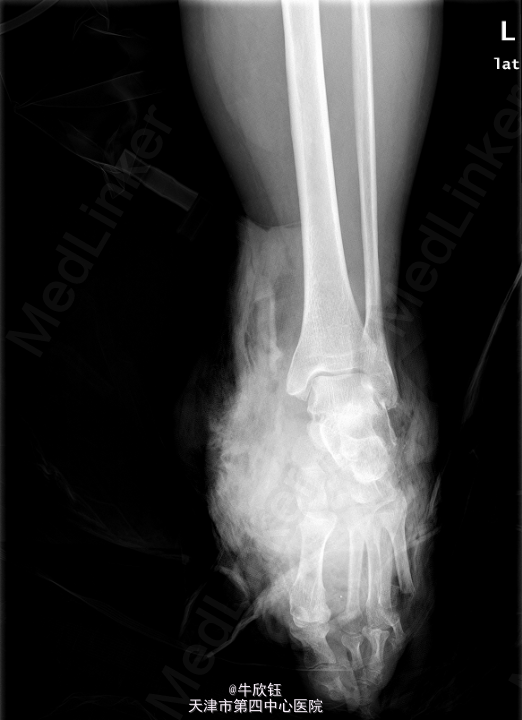

患者,女,71岁,因“外伤致左足出血疼痛伴活动受限1小时”入院。患者于1小时前意外车祸 致左足出血疼痛,血量多,疼痛呈持续性,难忍,伴活动困难,当即不能行走,无其他部位受 伤,足部大面积皮肤损毁。

左足出血肿胀明显,皮肤大面积损毁,局部散在瘀斑,左足活动受限,关节间隙压痛(+)。 我院X片:左腓骨下端骨折。左第5跖骨远端骨折,断端分离。左足诸跗骨间隙宽窄不一。左足 软组织肿胀明显。

初步诊断: 左足损毁伤 处理:全麻下行左小腿中段截肢术。

该病例左腓骨下端骨折严重,皮肤条件差。考虑保肢效果差,经讨论后家属选择截肢。